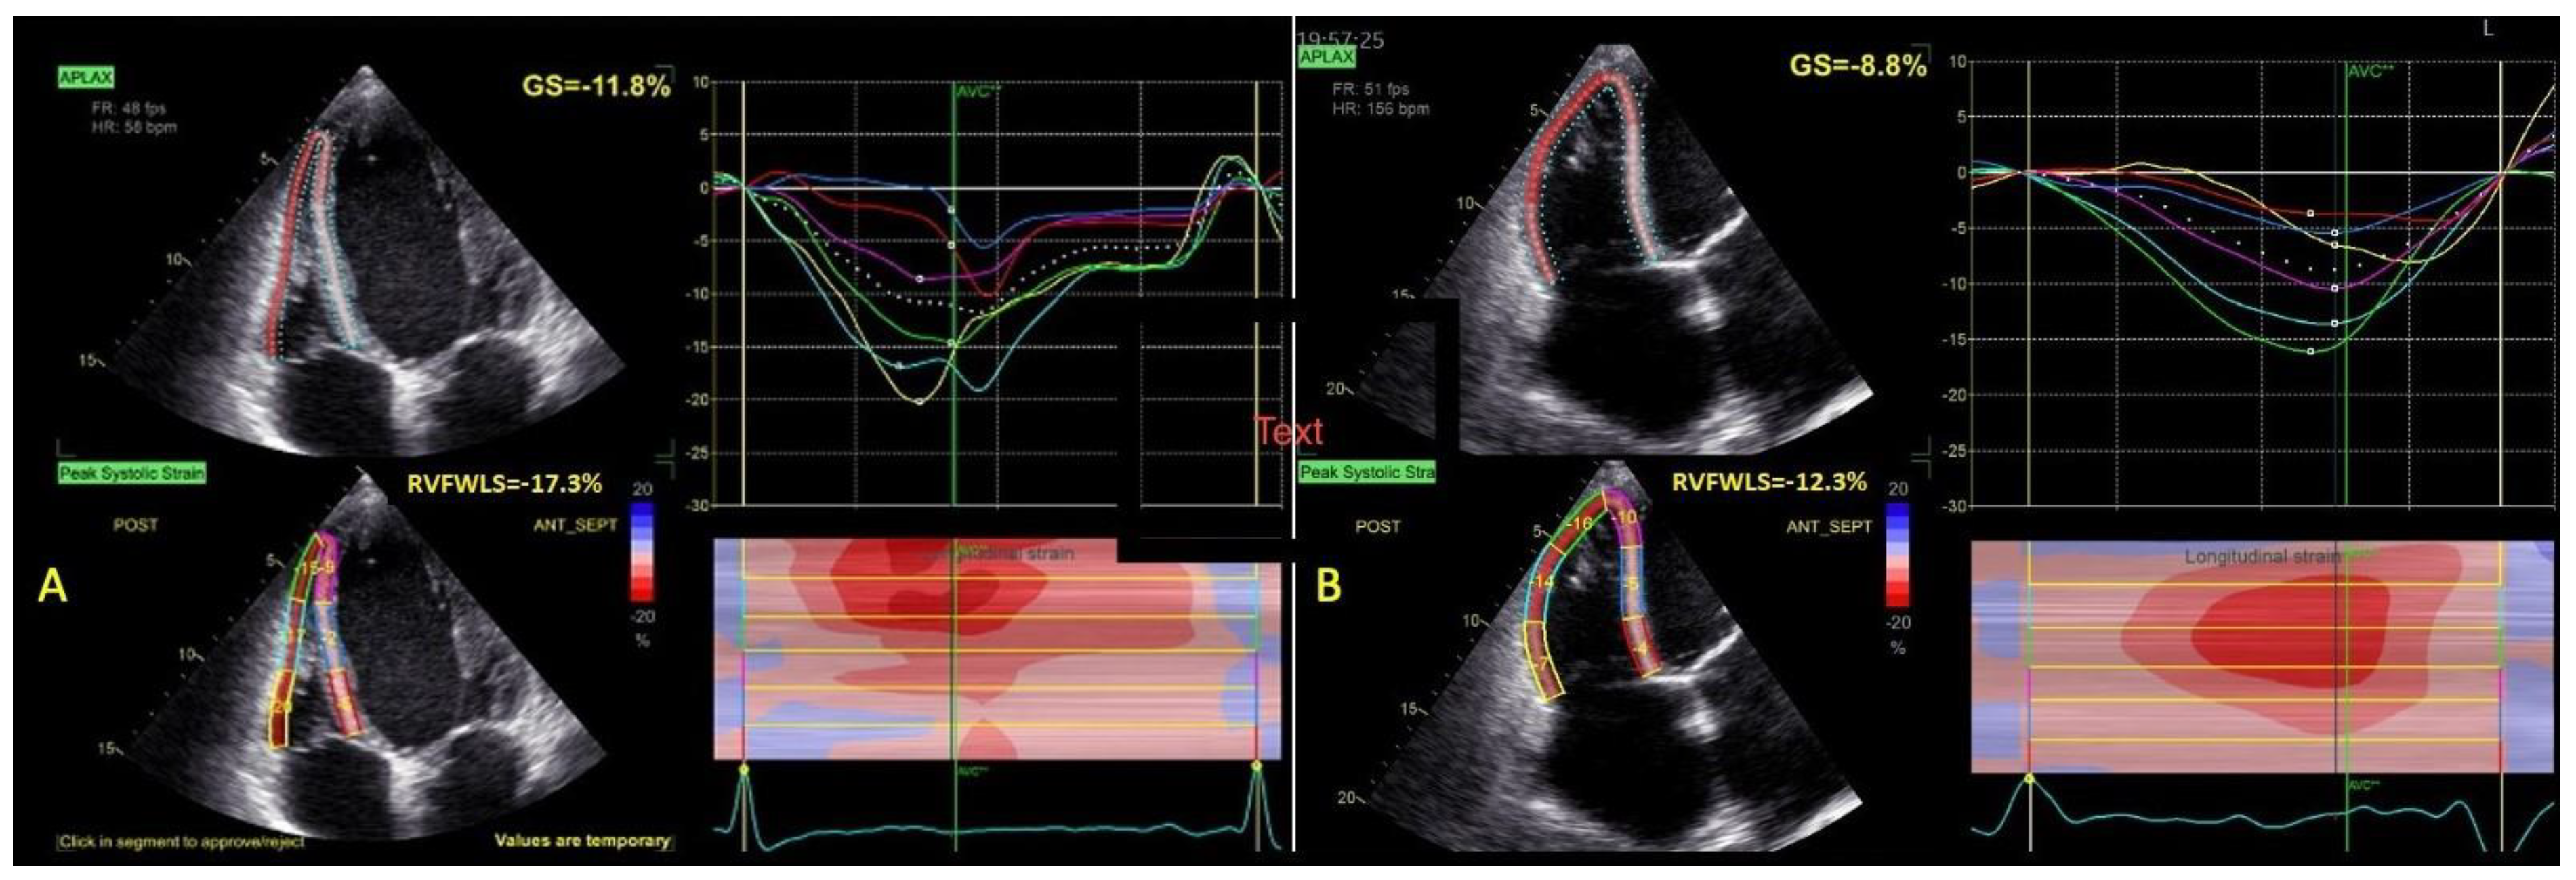

| LVGLS (%) | 7.9 ± 3 | 6.2 ± 2 | 0.008 |

| RVFWLS (%) | 17.2 ± 7 | 13.2 ± 5 | 0.004 |